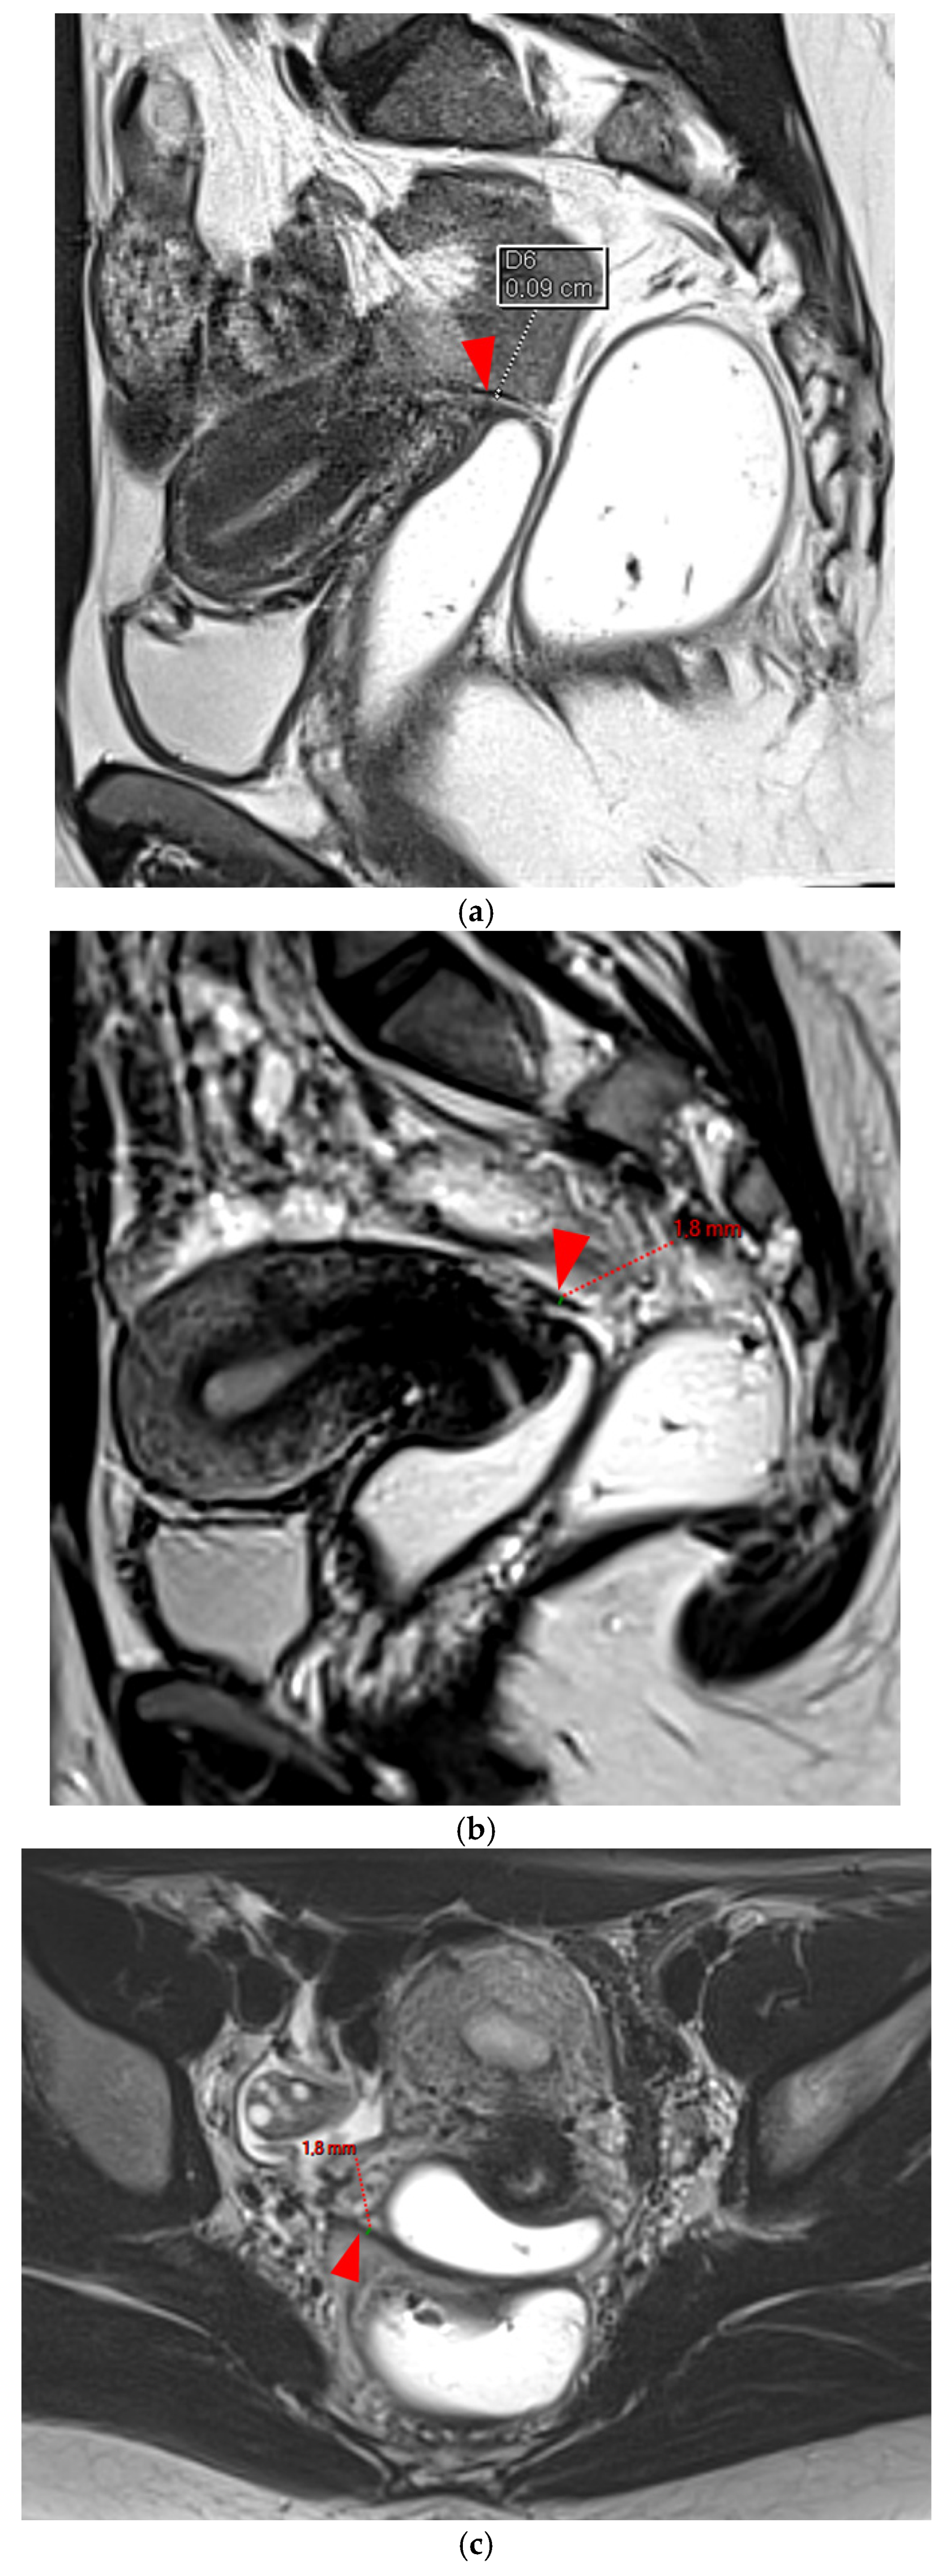

Figure 13. Pelvic MRI scan of a patient with a HTD type 6 right USL. (a,b) Axial (a) and sagittal (b) T2WI show a spiculated nodular hypointense lesion (arrows) located in the right cardinal ligament (a.k.a. Mackenrodt ligament), affecting the uterovaginal nerve plexus, a component of the inferior hypogastric plexus. Note the steep vertical orientation of the right proximal USL (arrowhead), which is reclassified from type 3B to type 6 due to this so-called “visceral” involvement.

A type 6 USL is associated with adjacent pelvic “visceral” involvement in a broad sense. It most commonly affects the digestive tract (Figure 8 and Figure 9), with the rectum and rectosigmoid junction wall thickening: in this case, the lesion often appears as a “medallion-shaped” protrusion into the lumen. Less frequently, the urinary tract is affected (Figure 9 and Figure 10), involving the muscular layer of the bladder or even the distal ureter at the level of the common iliac artery, with stenosis potentially leading to upstream hydronephrosis. More rarely, as USLs are also close to nearby pelvic nerve structures (Figure 11), contiguous involvement of the inferior hypogastric plexus located in the sacro-recto-genital septum (a.k.a. Delbet sagittal fascia) beneath the distal two-thirds of the USL, or exceptional involvement of the sciatic nerve adjacent to the pelvic wall, is possible (Figure 12, Figure 13 and Figure 14).